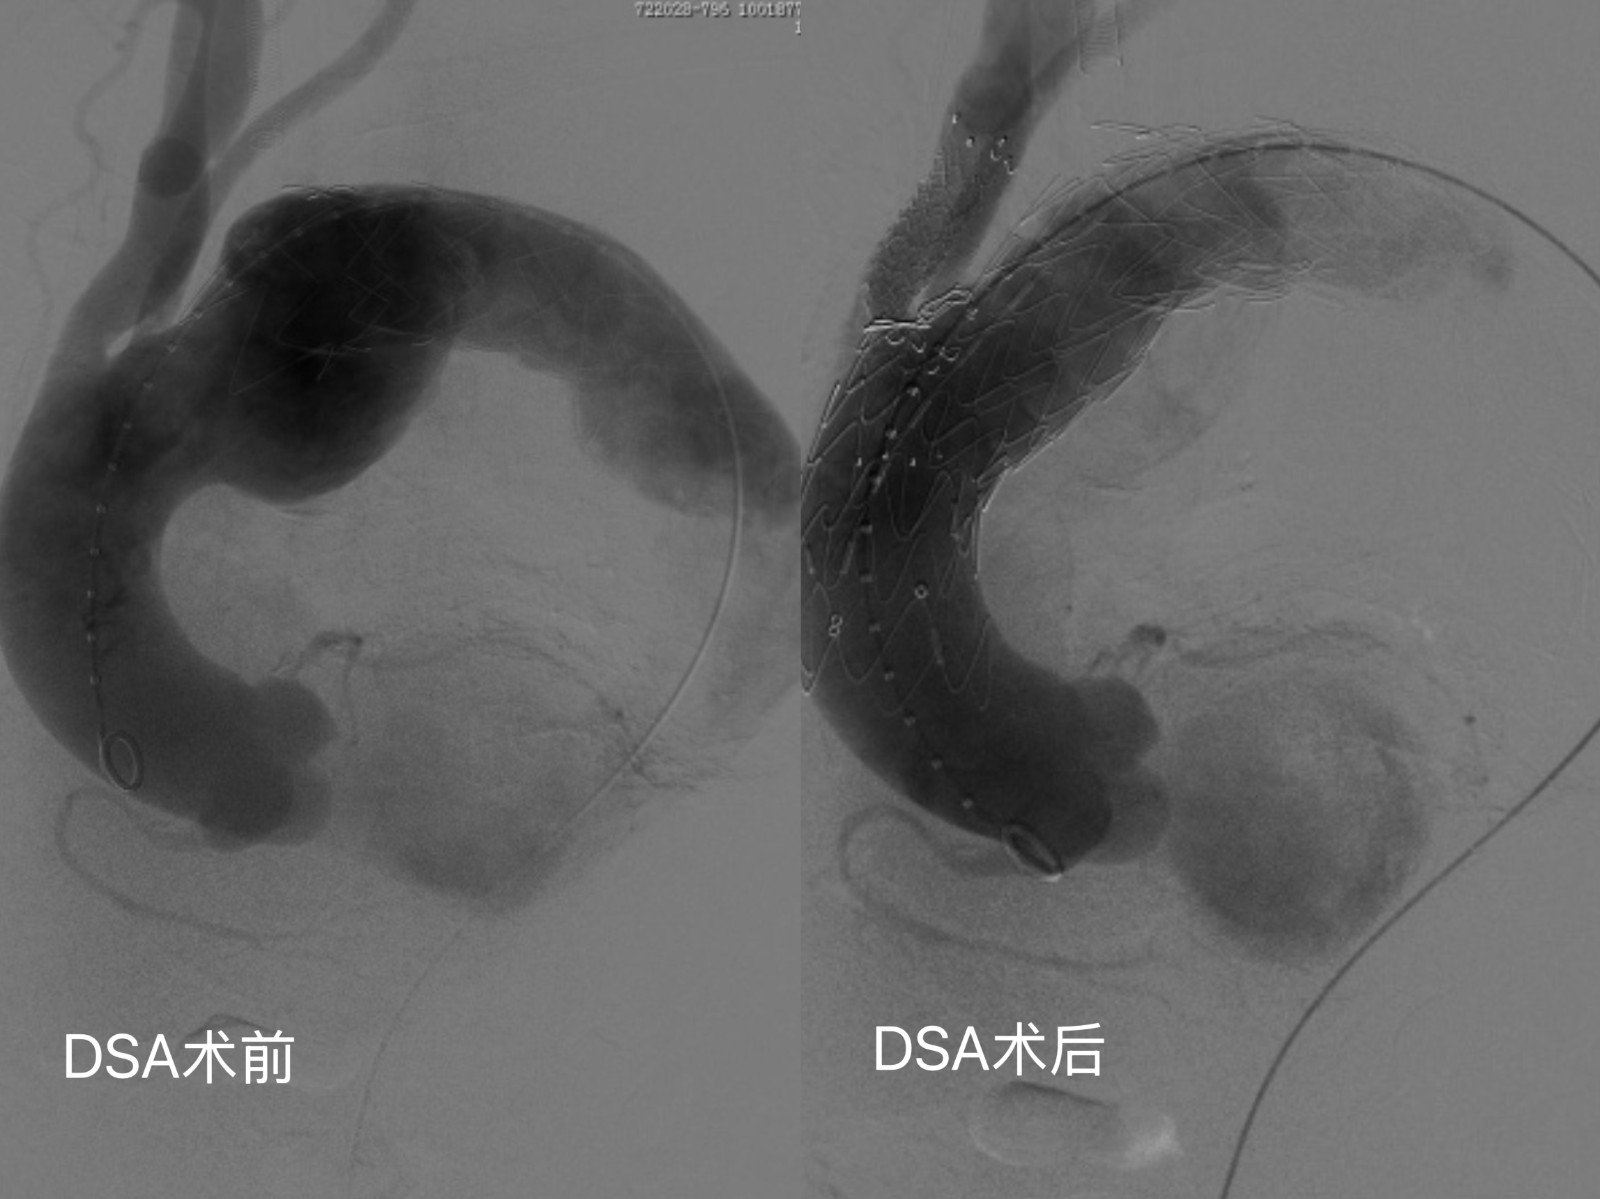

手术当日,在模型的基础上,手术团队预先在定制的主动脉支架上进行了精准“开窗”。这些“窗口”的位置、大小、角度都经过精密计算,确保植入后能与患者自身的分支血管完美对接,在隔绝动脉瘤的同时,完美保留了通往大脑和上肢的血流,避免脑梗等严重并发症的发生。“开窗”完成后,主刀医生再通过股动脉将精心准备的“开窗”支架输送至主动脉弓病变部位。在X光透视和术前3D模型的精准引导下,支架如同被施以“魔法”,一次释放到位,完美覆盖了动脉瘤,支架上的“窗口”也精准地对上了分支血管的开口。术后造影显示:动脉瘤被完全隔绝,而重要分支血管血流通畅无阻,手术获得圆满成功!

整个手术过程出血极少,术后胡爷爷很快在监护室苏醒,第二天转回病房。目前,胡爷爷恢复良好,精神状态佳,不日即将康复出院。他和家人激动地表示:“没想到这么大的手术,恢复得这么快!真是太感谢医院的专家们了,是你们给了我第二次生命!”